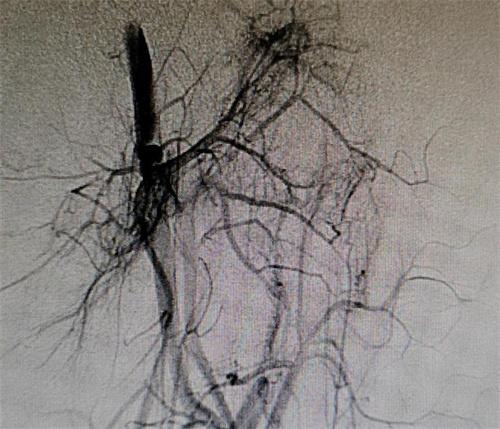

在下肢做完磁共振和血管造影等檢查之后,發現左腿血管多處都有畸形動脈,靜脈之間有較為異常連接的通道,一部分血液循環過程中較為偷懶,走了一條捷徑,使得各個組織之間在營養供給上是很不均衡的。目前這個病重不能夠完全治愈,但可以控制病情發展縮小差異。